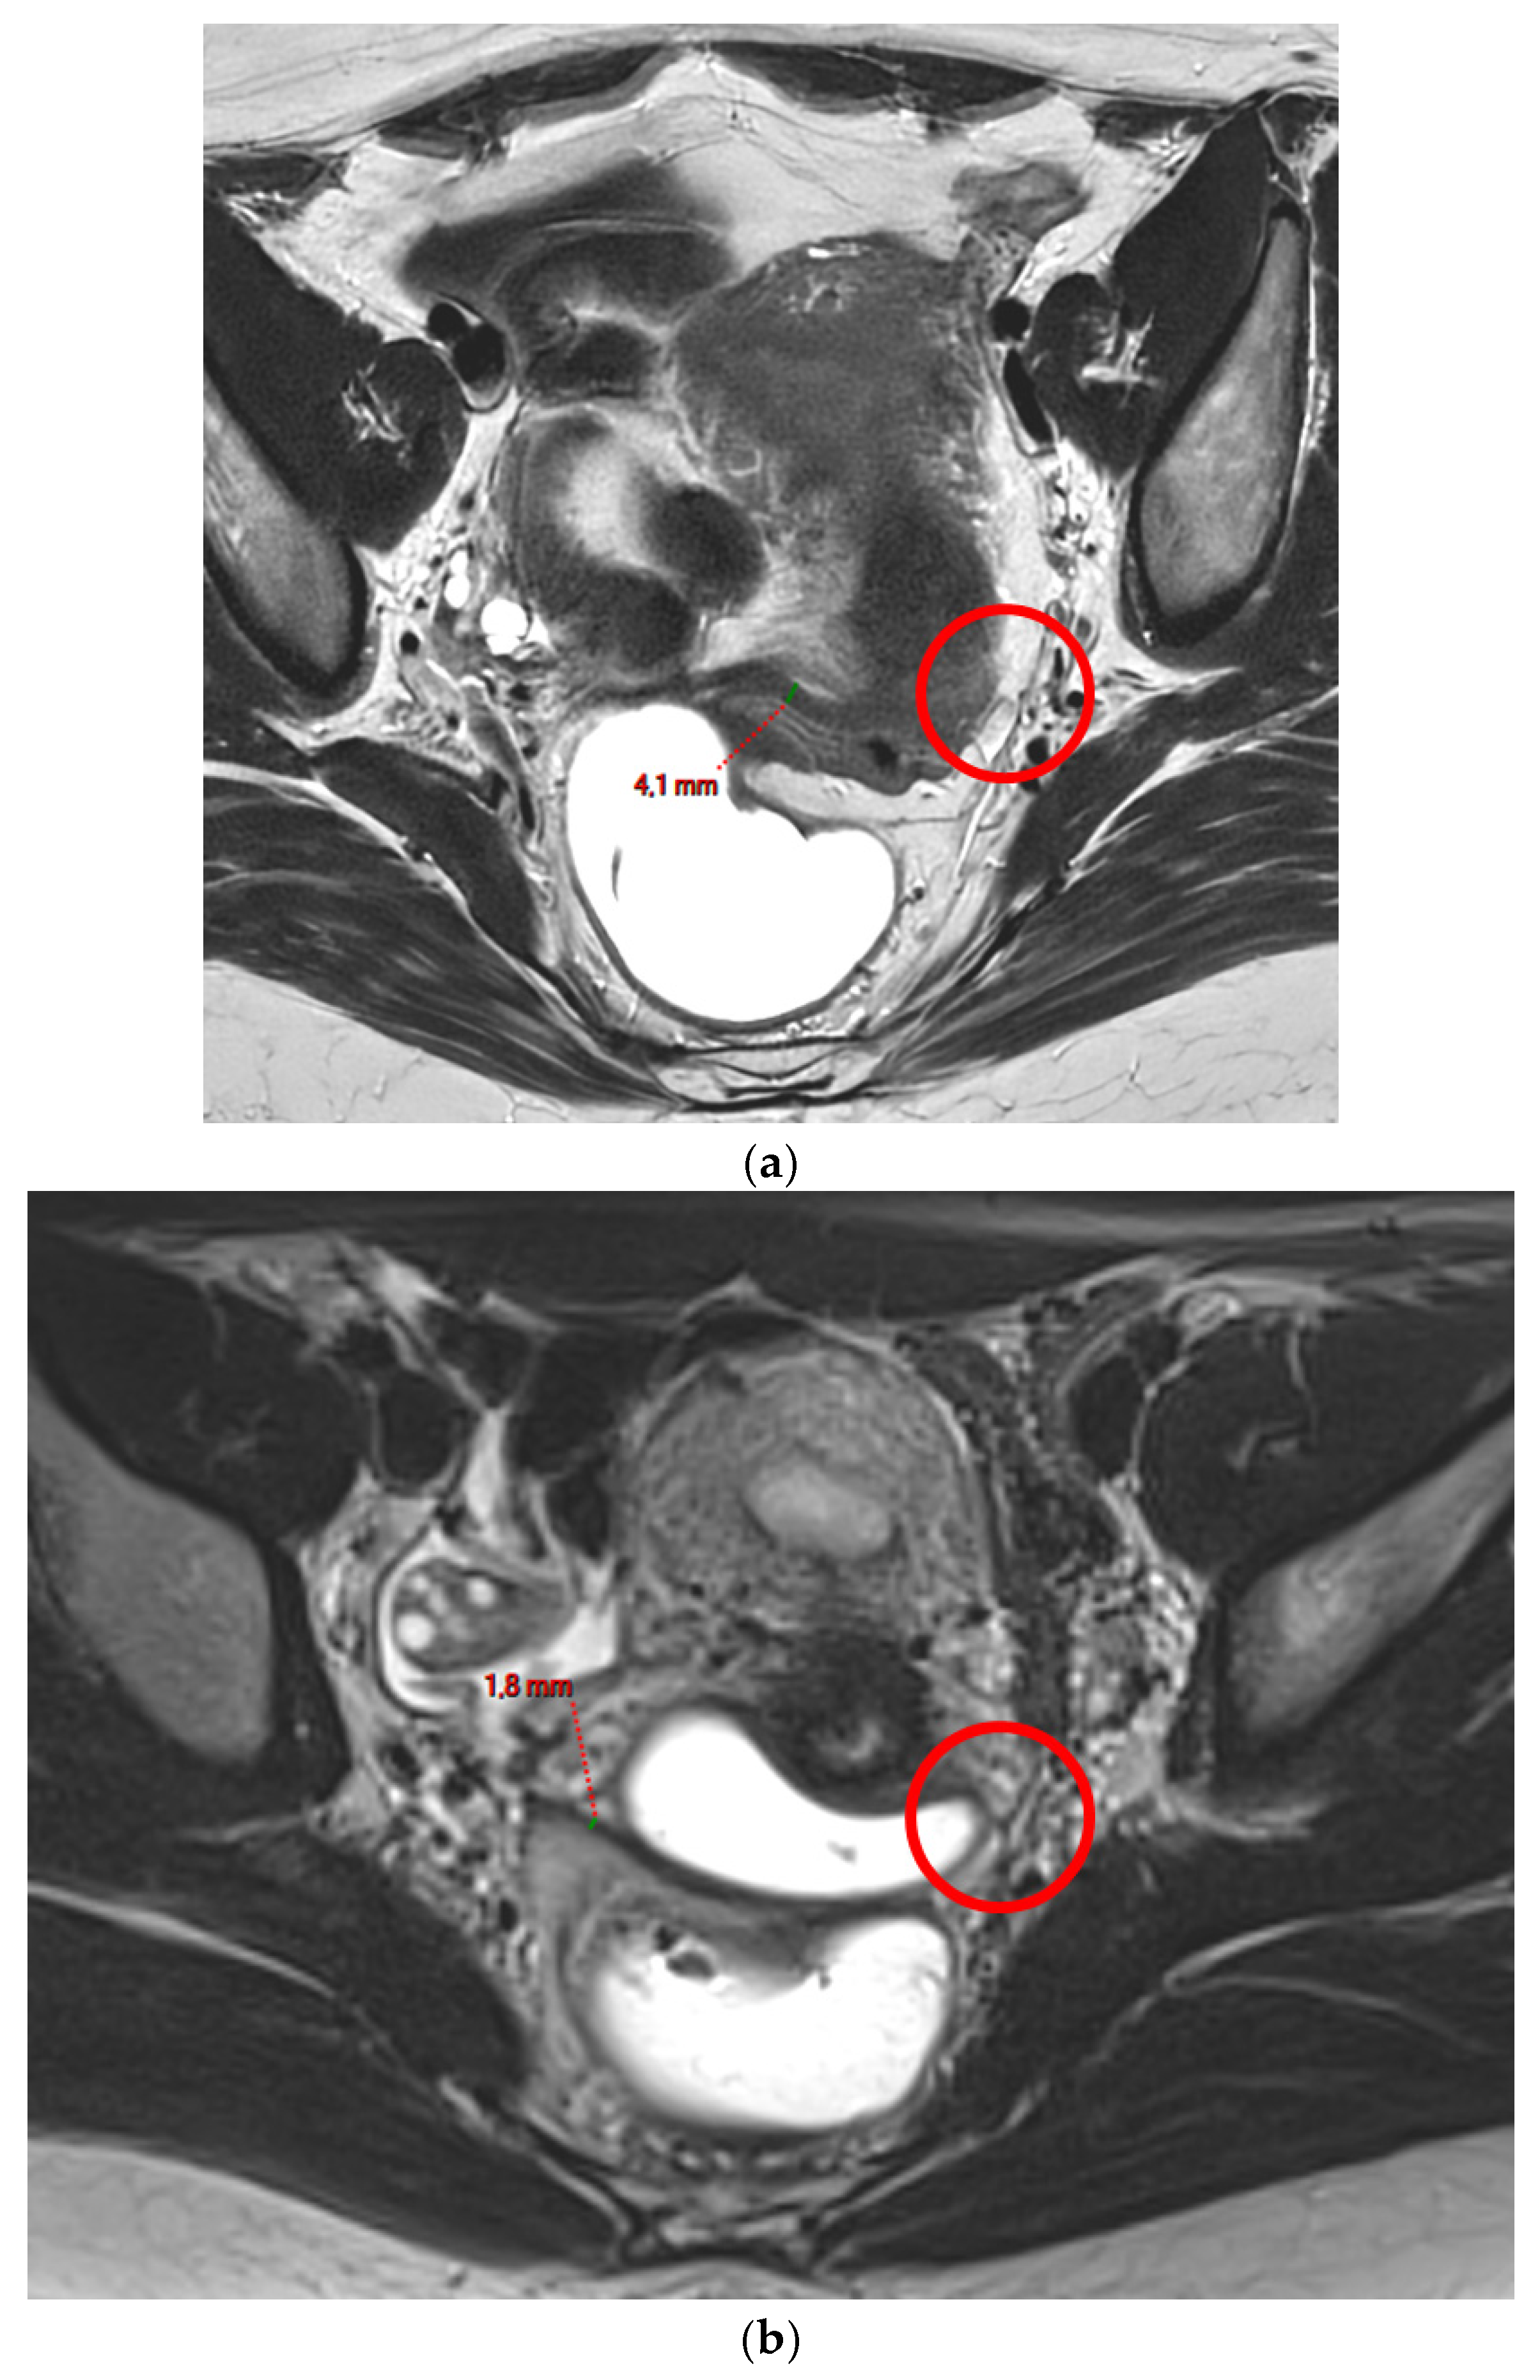

Figure 1. Pelvic MRI scans of two patients with non-visible left USLs (HTD type 1). (a) Axial T2WI shows a visible and measurable right USL but a non-visible left USL (red circle). (b) Axial T2WI shows a visible and measurable right USL but a non-visible left USL (red circle).

A type 1 USL (Figure 1) is not visible on MRI scans.